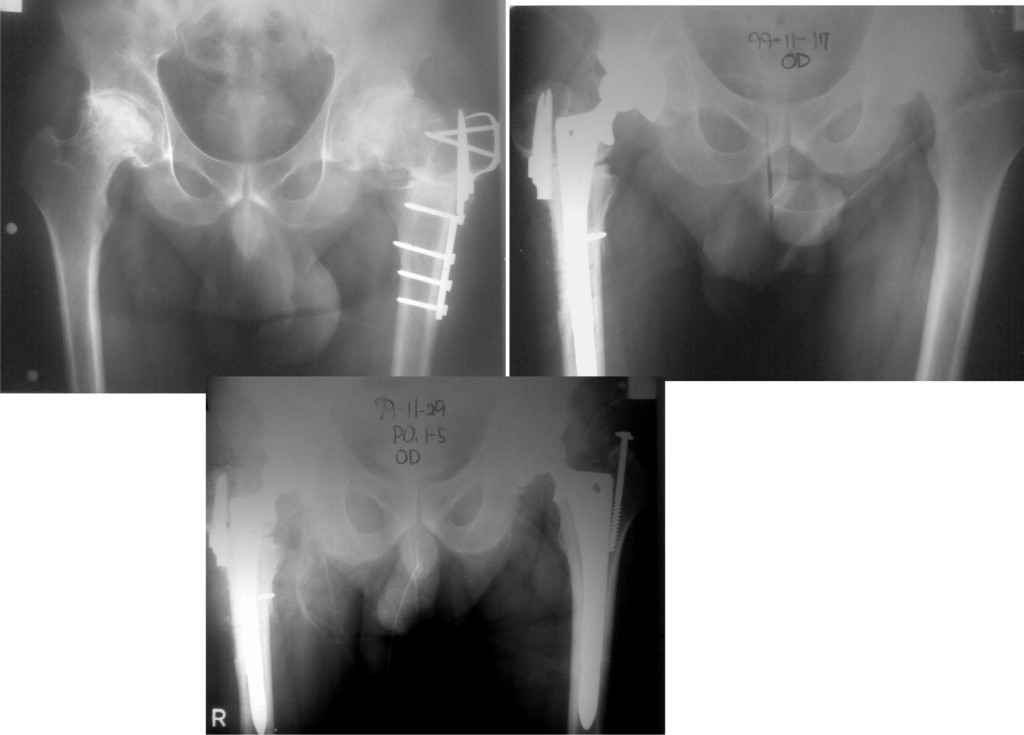

У меня опыт по эндопротезированию совсем небольшой. Еще 5 лет тому назад у нас в городе не было протезирования. Во вложении снимки одного больного из нашего города. который оперировался в 1999 году в Южной Корее. разница по времени замены второго сустава 11 дней. Больной по настоящее время ходит без проблем, особых жалоб не предъявляет, весит он 98 кг. Может быть есть смысл подождать, по наблюдать а оперировать никогда не поздно.

К сожалению на снимках чашки просматриваются плохо. Вопрос: слева в бол. вертеле винт(на снимках после ТЭП). Это доступ с отсечением или что?

дело в том,что на снимках после замены второго сустава прослеживается ход дренажной трубки, т.е снимок контрольный сразу же после операции. Если этот доступ был с отсечением большого вертела, то не прослеживается линия остеотомии. По началу я тоже так и подумал, я считаю, что винт выполняет роль клина для стабильности ножки. Что касается качества снимков то согласен, но судя по контурам вертлужного компонента он напоминает ваш снимок.

Сегодня все-таки выполнили ревизию вертлужного компонента. Действительно, чашка держалась только по окружности, относительно легко удалилась. Так что тактику считаю правильной, ибо ловить при такой установке особо нечего было. Нестабильность в блишайшее время была бы обеспечена. Снимки после переустановки в приложении. Качество, конечно не ахти какое, это сделано на столе на плохом аппарате. Посадка проконтролирована визуально через центральное отверстие. Головку не снимали, оставили короткую. Если до ревизии длина левой ноги была +1 см, то после D=S. Теперь осталось молиться, чтобы не было осложнений. Вроде бы все прошло не травматично.